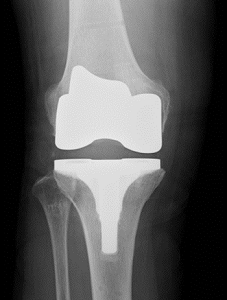

人工膝関節は表面に金属を置換することでこの痛みを取り除き、膝関節を正常に機能させる手術です。症状の進んだ膝関節を人工膝関節に置き換える手術を人工膝関節置換術といいます。人工膝関節手術には膝関節軟骨部分をすべて置換する人工膝関節全置換術と痛んだ内側部分または外側部分をかえる人工膝関節部分置換術の2種類が存在します。

人工膝関節は下図のように、主に大腿骨部、脛骨部の部品で構成されています。大腿骨部は金属製です。脛骨部は耐久性にすぐれたプラスチックでできており、軟骨の役割をして、スムーズな関節の動きとなります。また当院では世界でも最先端のロボットを導入することで、患者さん一人一人に対してオーダーメイドの人工膝関節を行っております。